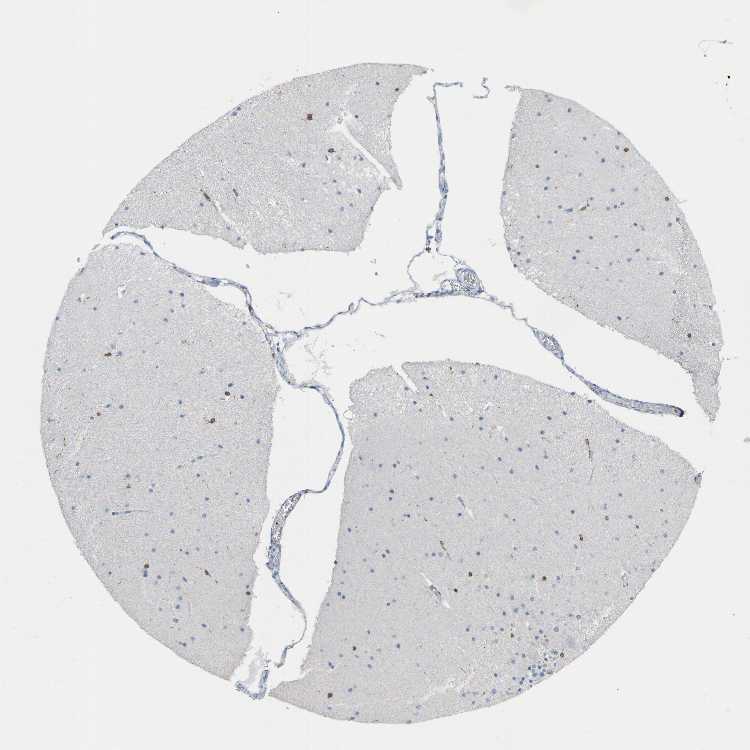

BRAIN CEREBELLUM Show tissue menu

CEREBELLUM - Expression summary

CEREBELLUM - Antibody stainingi

Antibody staining in the annotated cell types in the current human tissue is reported as not detected, low, medium, or high, based on conventional immunohistochemistry profiling in selected tissues. This score is based on the combination of the staining intensity and fraction of stained cells.

Each image is clickable and will lead to virtual microscopy that enables deeper exploration of all samples and also displays staining intensity scores, fraction scores and subcellular localization as well as patient and tissue information for each sample.

Antibody HPA002834Antibody CAB020315

Purkinje cells Not detectedNot detected

Cells in granular layer LowLow

Cells in molecular layer LowMedium